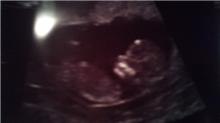

flot navn.. ! (: men endnu engang tillykke med hende!! ja det vil jeg! ved bare ikke hvor tidligt man kan se kønnet? ..

Nogen steder siger de at de kan se det fra uge 14, men jeg tror nærmere det er fra uge 17..

Men er ikke helt sikker...